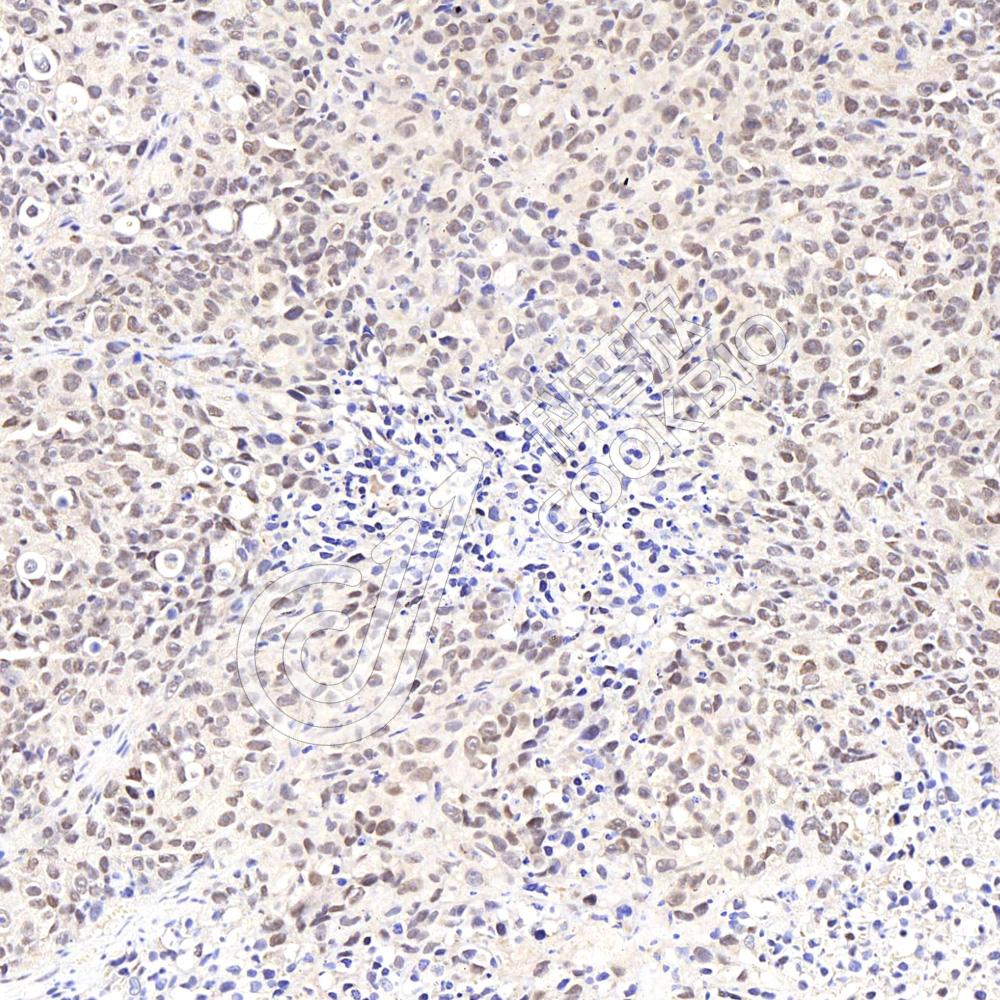

IHC检测Cdc25A蛋白(货号 K133849).

样品: 小鼠乳腺癌, 4%多聚甲醛 (货号KSG1101) 固定12-24小时.

抗原修复: 柠檬酸抗原修复液(干粉, pH 6.0) (KSG1201), 98℃, 20分钟.

—抗: 1: 2300稀释, 4℃ 孵育过夜.

二抗: S-vision免疫组化多聚二抗(山羊抗兔),即用型 (货号KB3906), 室温孵育20分钟.